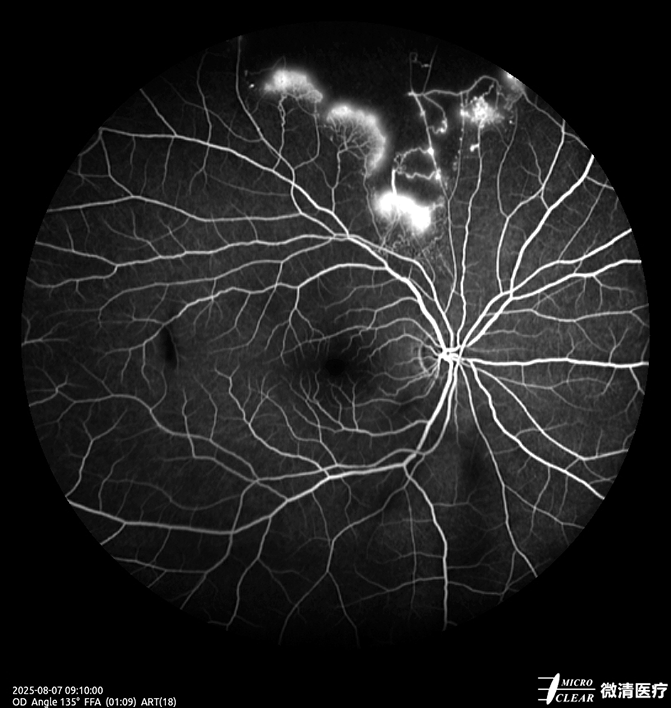

8.视网膜分支静脉阻塞/廊坊市广阳区眼科医院

1758873743787423.png

1758873750670754.png

1758873757205088.png

1758873762860454.png

1758873770751246.png

(1) 一、患者基本信息:女性,69岁

(2) 二、主诉:右眼视物不清10天。